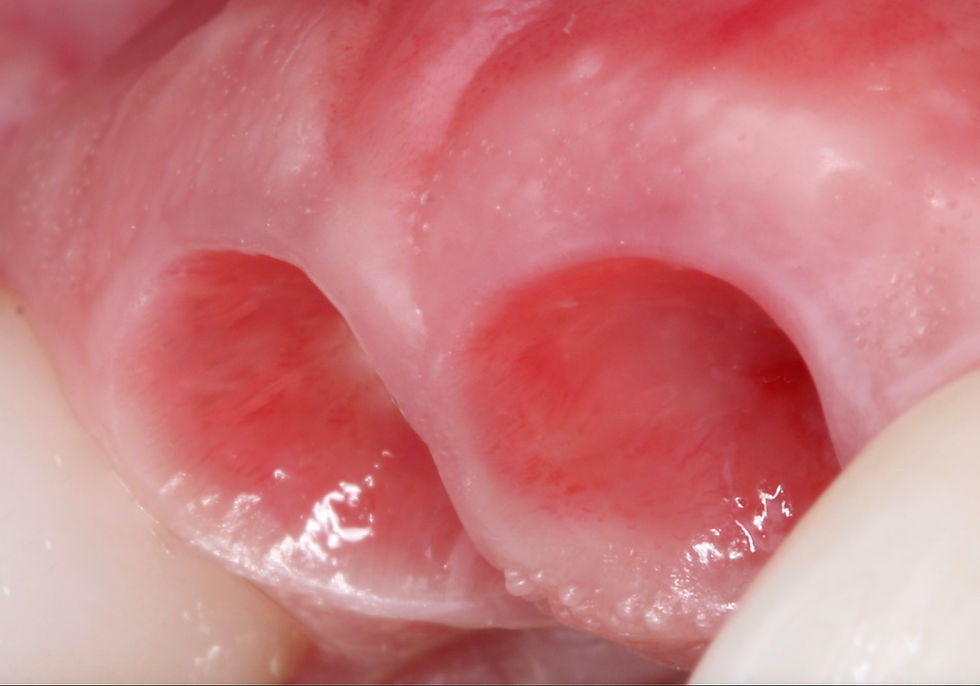

O perfil de emergência é a forma tridimensional com que a restauração protética emerge do implante em direção à cavidade oral. Em termos clínicos, é o contorno do componente protético (provisório ou definitivo) que molda e sustenta os tecidos peri-implantares, influenciando diretamente a arquitetura tecidual, a estética cervical e o sucesso biológico a longo prazo.

Trata-se de uma zona entre o implante e a cervical da coroa protética, que deve respeitar os limites anatômicos dos tecidos moles.